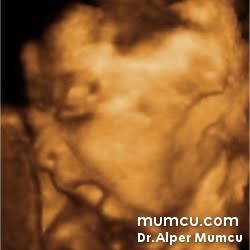

3 Boyutlu ultrason resimleri

Bu sayfadaki fotoğraflar degişik zamanlarda ve farklı hastalarda Dr. Alper Mumcu tarafından çekilmiştir.

13 haftalık gebelik